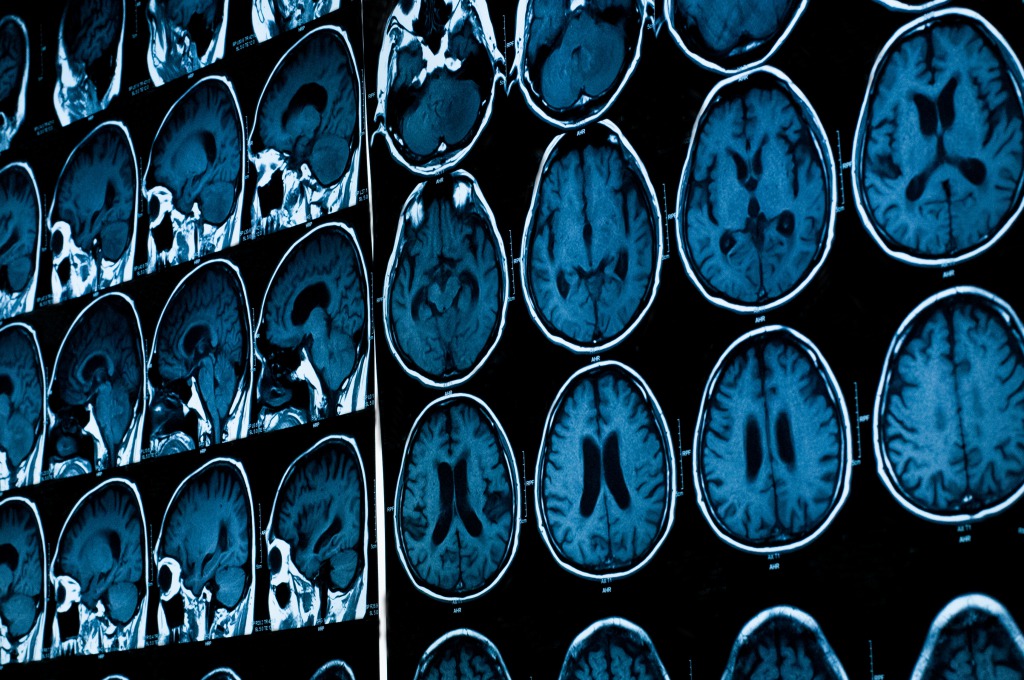

- 構造的および機能的な変更:

脳画像処理 は、アルコール依存が皮質灰白質の喪失などの構造的損傷、および脳活動や神経化学的プロセスの機能的変化を引き起こすことを示しています。これらの変化は、思考能力の低下、問題行動、依存症の進行と関連しています。 - 思考と記憶の障害:アルコールは、記憶を司る脳の領域(例えば、